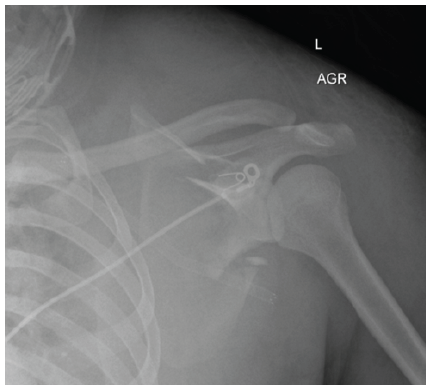

A 22-year-old active-duty male sustained polytrauma following a high-speed motorcycle collision, resulting in fractures of the left radius and ulna, left scapula, left tibia and fibula, and left proximal femur, as well as cervical spine fractures and a left subclavian artery injury. Initial treatment occurred at a community hospital before transfer to a Level II military trauma center. Further evaluation revealed a comminuted left scapular body fracture with scapulothoracic dissociation. Neurologic examination raised concern for pan-brachial plexus injury, with complete motor and sensory deficits in the affected extremity. Imaging demonstrated transection of the suprascapular nerve branch to the supraspinatus, while the branch to the infraspinatus remained anatomically intact but non-functional. Radiographs of the left shoulder were collected, and high-resolution CT imaging of the scapula was used to render a 3D reconstruction of the scapular fracture. Imaging demonstrated a comminuted left scapula fracture with fractured margins isolating the glenohumeral joint from the scapular body (Fig. 1 and 2). Given the goals of pain control and shoulder girdle stabilization, operative management was indicated.

Figure 1: Pre-operative anteroposterior radiograph of the left shoulder demonstrating a comminuted left scapula fracture with displacement and medialization of the glenoid segment.